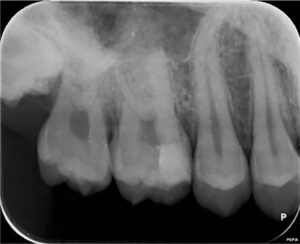

治療後1カ月

歯髄保存療法1か月後のレントゲン写真です。MTAの層が厚く、強度出すためにを一部のMTAを除去してコンポジットレジンの層が厚くなるように調整しております。

特に状態は変わらず、歯の周りの組織にも異常は見られませんでした。

電気的な検査で神経は正常でした。

治療直後の2日ほどは少し痛みがありましたが以降は痛みなく経過しています。

治療後2カ月

歯髄保存療法2か月後のレントゲン写真です。特に状態は変わらず、歯の周りの組織にも異常は見られませんでした。

軽度の知覚過敏症状が見られました。

治療後3カ月

歯髄保存療法3か月後のレントゲン写真です。特に異常は見られませんでした。

知覚過敏症状は改善していました。